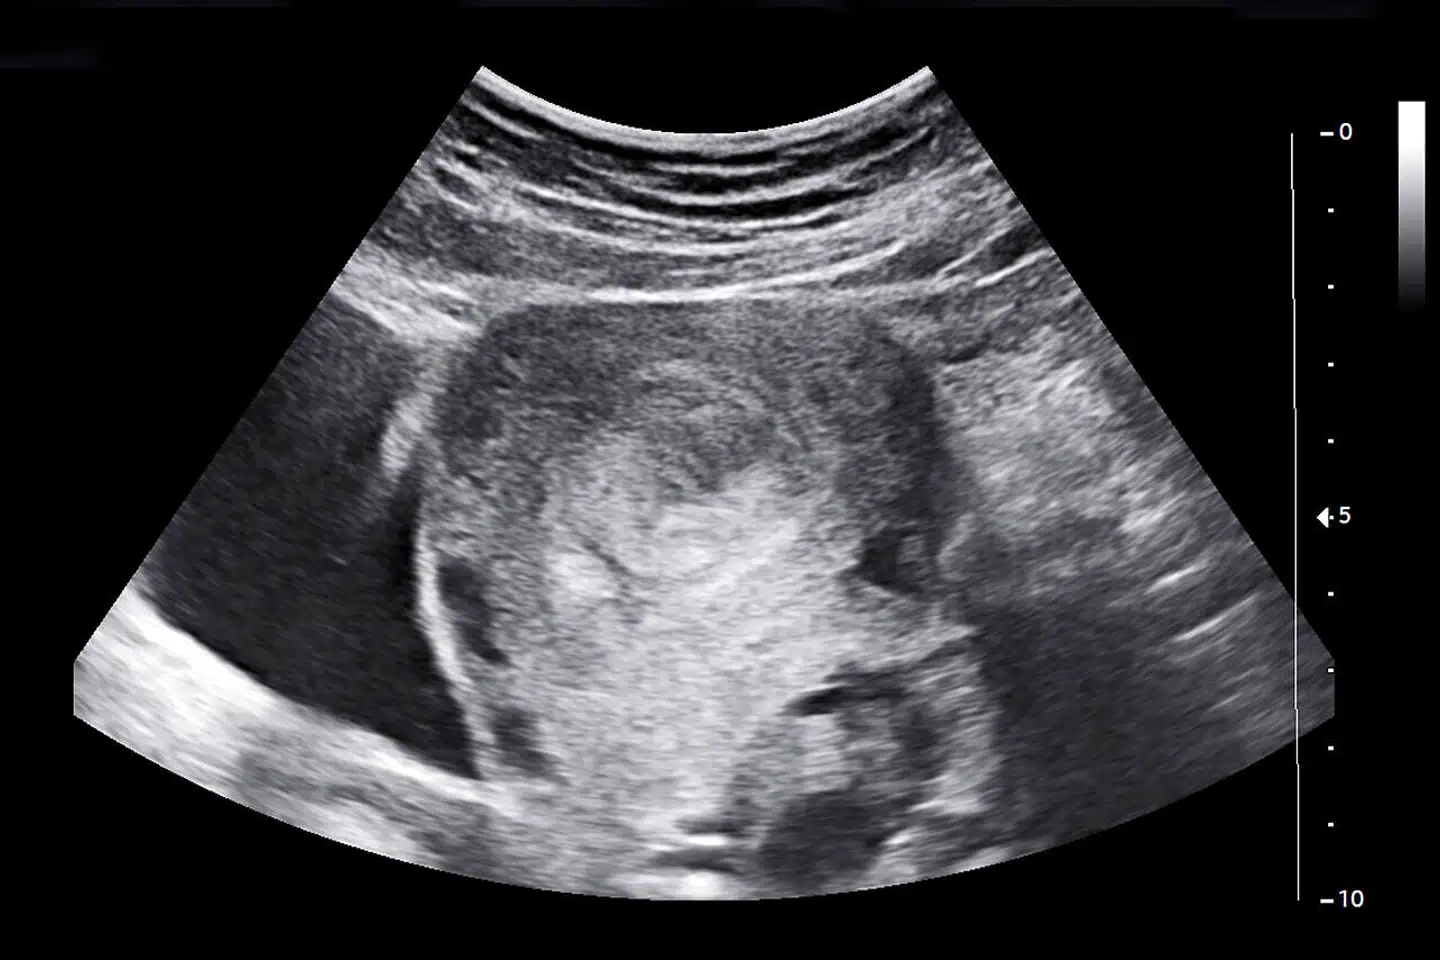

SELV om det ufødte barns eksistensberettigelse sjældent indrømmes, er abortaktivisternes årelange afvisning af fostrets rettigheder ganske forståelig. Ufrivillige graviditeter og kampen for fri abort har medført så stor smerte og så mange ofre, at det har krævet en vis form for hårdfør fornægtelse at få trumfet den skelsættende lovgivning igennem. Her var ikke plads til sarte hensyn. Måske er tiden moden nu. Sagen er jo, at når vi ser et billede af et foster allerede i 12. uge, er det umuligt ikke at få øje på et lille menneske i sin mest sårbare tilstand. Hvad det angår, har abortmodstanderne altid haft ret. Det går der ingen skår af nogen ved at erkende.